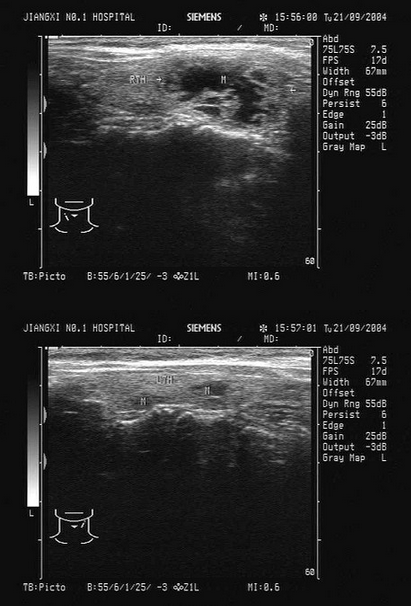

临床资料:男,50岁,自述胃癌术后3年余。超声综合描述:右锁骨上窝扫查可见数个长圆形低回声区,最大1.7cm×1.1cm,边界尚清,内回声欠均匀,部分互相融合,CDFI:内可见少许动脉血流信号。见下图及彩图。

超声提示()。

A.右锁骨上窝淋巴结结核

B.右锁骨上窝囊肿

C.右锁骨上窝肿大淋巴结(淋巴结转移瘤)

D.右锁骨上窝正常淋巴结声像图